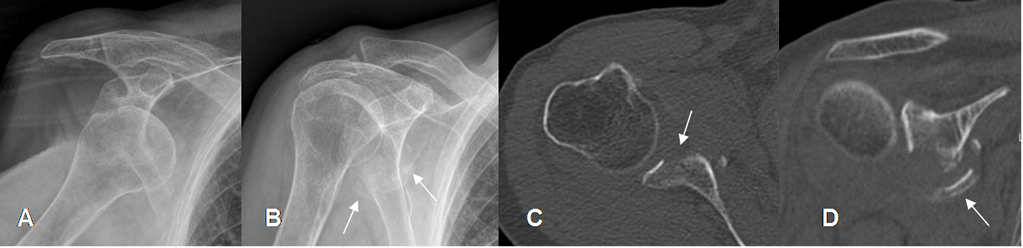

Fig 50 A. Lesión de Bankart.

A: Rx AP. Luxación anterior del hombro.

B: Rx AP. Después de la reducción, se aprecian fragmentos óseos por debajo de la glenoides.

C: TAC axial. Fractura del borde anterior de la glenoides, por Bankart oseo.

D: TAC reconstrucción coronal. Fractura de la glenoides inferior, con fragmentos desplazados.